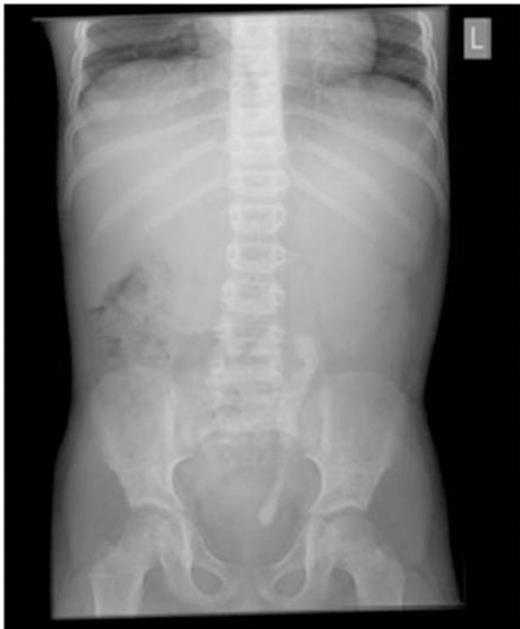

A 7-year-old boy was admitted for observation following non-accidental injury. He had an episode of painless haematuria as an inpatient. There was no history of urinary tract infections or renal colic. Clinical examination was unremarkable. Urine culture showed no growth and blood investigations were normal. Ultrasonography demonstrated left hydronephrosis and a 2cm echogenic area with acoustic shadow in the proximal ureter, consistent with a ureteric calculus. Plain radiography astonishingly revealed a large 7cm radio-opaque shadow in the line of the left ureter extending from the left pelvi-ureteric junction to the mid-ureter, and a second 4cm opacity in the left distal ureter (Fig 1).

Plain abdominal radiograph demonstrating large opacity extending from the left pelvi-ureteric junction to the mid ureter, and a smaller opacity in the distal ureter.